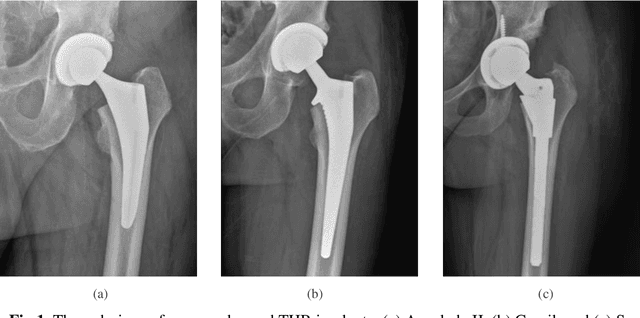

Abstract:Identifying the design of a failed implant is a key step in preoperative planning of revision total joint arthroplasty. Manual identification of the implant design from radiographic images is time consuming and prone to error. Failure to identify the implant design preoperatively can lead to increased operating room time, more complex surgery, increased blood loss, increased bone loss, increased recovery time, and overall increased healthcare costs. In this study, we present a novel, fully automatic and interpretable approach to identify the design of total hip replacement (THR) implants from plain radiographs using deep convolutional neural network (CNN). CNN achieved 100% accuracy in identification of three commonly used THR implant designs. Such CNN can be used to automatically identify the design of a failed THR implant preoperatively in just a few seconds, saving time and improving the identification accuracy. This can potentially improve patient outcomes, free practitioners time, and reduce healthcare costs.